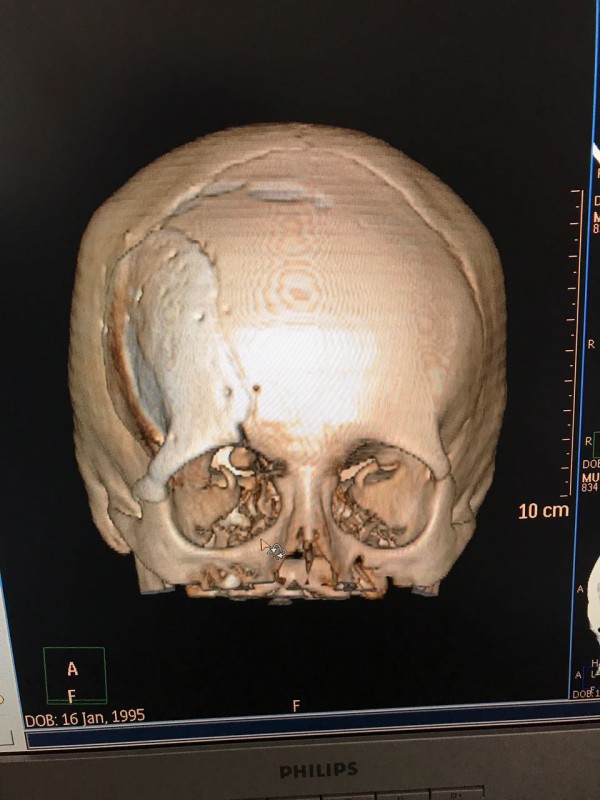

Как рассказал врач-нейрохирург городской клинической больницы № 7 Алматы Константин Ли, предварительный диагноз пациента - "фиброзная дисплазия лобной кости справа", то есть опухолевое поражение костей черепа. По его словам, сложность и уникальность операции в том, что опухоль плотно соприкасалась со зрительным нервом.

"Компьютерная томография показала, что костная опухоль поражала лобную кость и "крышу" орбиты глаза, которая, в свою очередь, сдавливала глазное яблоко. Чтобы убрать опухоль, потребовалось немало времени. Наша задача была сохранить глазное яблоко, зрительный нерв и сосуды. Если неправильно провести операцию и неправильно закрыть дефект, то в последующем это может привести к эстетической неполноте и асимметрии лица. Уникальность еще и в том, что в операции применялась 3D-стереолитография, которая делается только в Алматы", - рассказал он.

Снимок черепа. Опухоль с левой стороны. Фото предоставлено Константином Ли